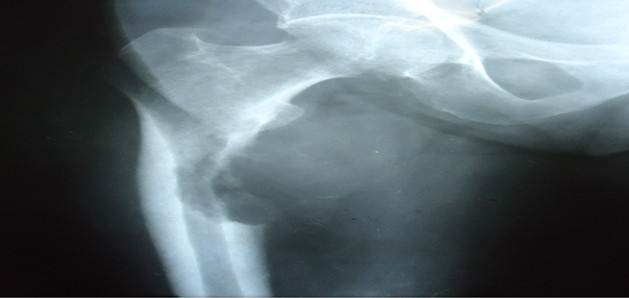

El segundo estadio es de vital importancia, para evitar la FP, que de ocurrir se produce la salida de células tumorales al hematoma fracturario y de allí al organismo. Las FP tienen cuatro características: son causadas por trauma mínimo o de forma espontánea, presencia de dolor o síntomas previos en la zona, trazo radiológico transversal y presencia de enfermedad previa local o sistémica (Figura 2). 25,26,27

En la región de la cadera el riesgo de FP es alto si reúne los siguientes requisitos: tumor mayor de 2,5 centímetros, que ocupe más del 50 % del diámetro óseo, fractura del trocánter menor y fallo del tratamiento con radioterapia. 29,30,31

Capanna R y Campanacci DA, 32 estiman el riesgo de FP cuando existe afección de más de un 50 % del diámetro cortical en los planos coronal y longitudinal (Figura 3).